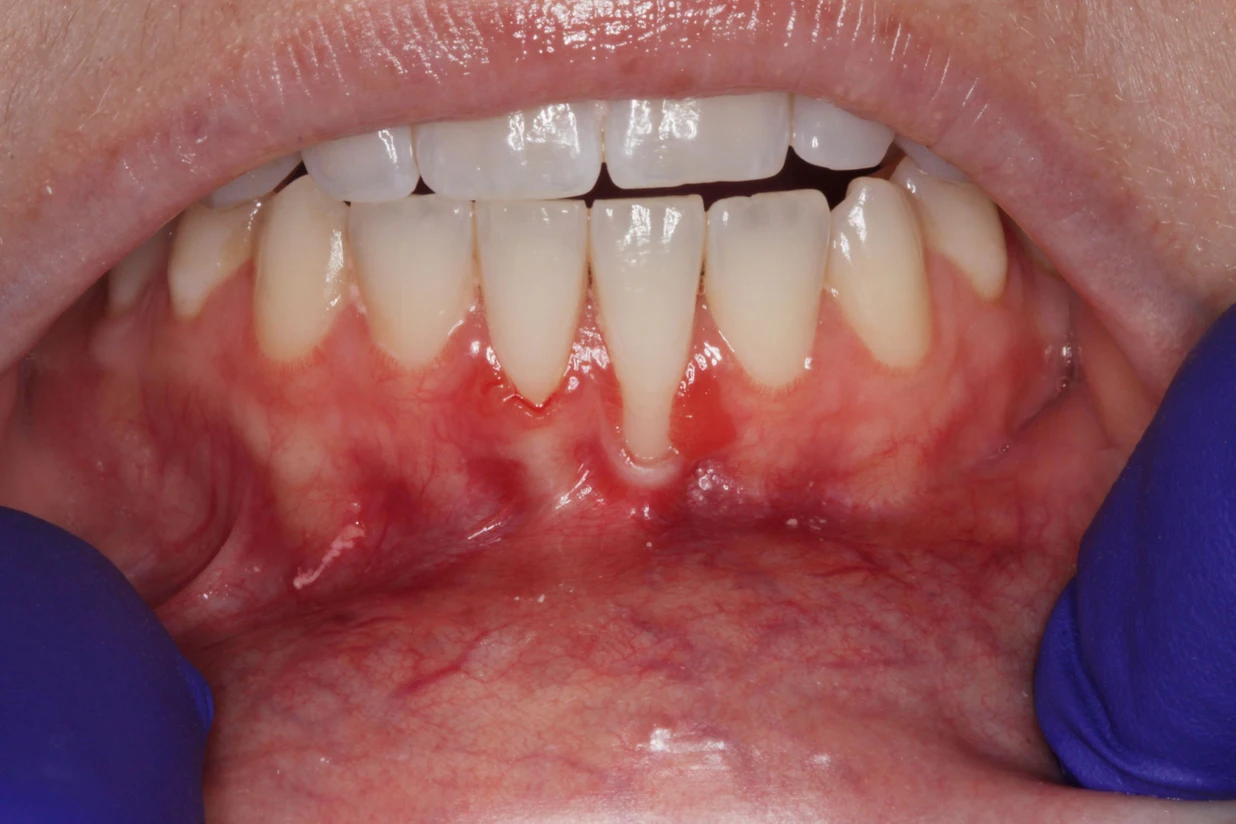

Drs. Gifford, Trylovich, Mantor and Irving provide soft tissue grafting to restore receded gums and improve the health and appearance of your smile. When you receive a soft tissue graft, our periodontists will carefully examine your mouth to determine the optimal placement of the graft and ensure the best possible results. Call Periodontics Limited today to schedule your consultation and learn more about soft tissue grafting in Las Vegas, Henderson and Summerlin, Nevada.